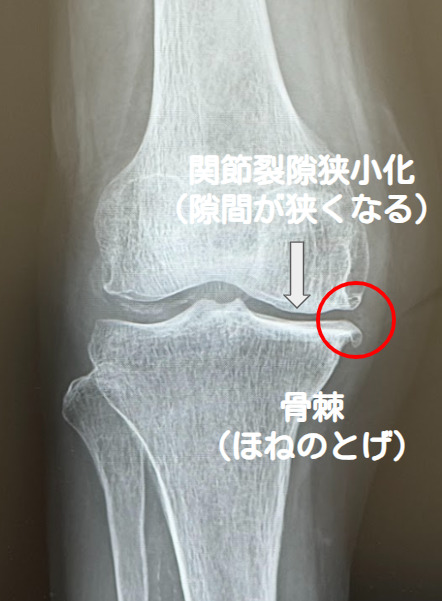

基本となるのはレントゲン検査です。立って撮影することで、関節の隙間の狭さ、骨のトゲ(骨棘)、骨の硬化、骨の中にできた空洞(骨嚢胞)、O脚やX脚の程度などを評価し、病気の進行度を分類します。必要に応じてMRI検査を行い、半月板や軟骨、靭帯の状態を詳しく調べます。他の病気との鑑別のため、血液検査や関節液検査を行うこともあります。